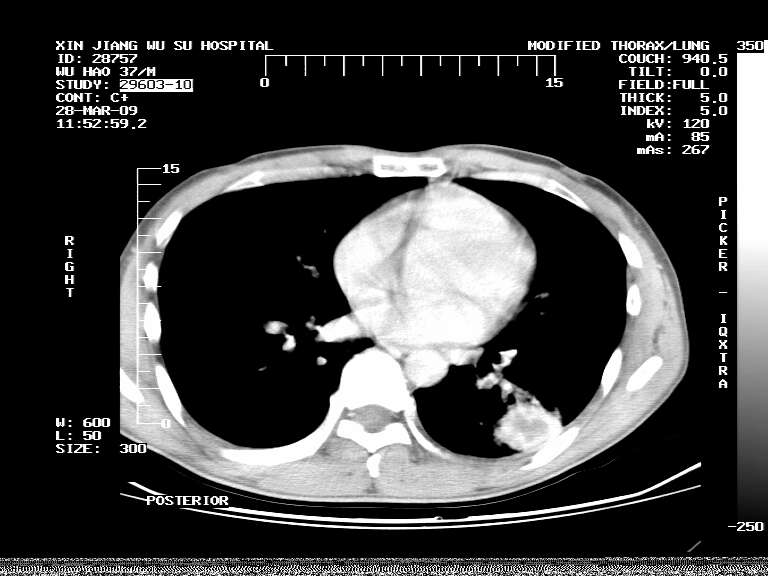

男,37岁,体检胸透发现阴影。

患者体检发现 无症状 左肺下叶占位,边缘模糊,可见血管聚束、分叶、胸膜牵拉,增强呈不均匀性强化。 首先考虑左肺下叶周围型肺癌,建议穿刺活检。

患者体检发现 无症状 左肺下叶占位,边缘模糊,可见血管聚束、分叶、胸膜牵拉,增强呈不均匀性强化。 首先考虑左肺下叶周围型肺癌,建议穿刺活检。支持!

左肺下叶见一结节病变,边缘欠清不光滑,与胸膜粘连且胸膜局限性增厚,注药后呈环形强化,动脉期壁呈明显点环状强化,静脉期壁强化减低,中心密度低无强化,灶周无明显的卫星灶和水肿区(晕征)---考虑周围性肺癌,不除外感染性病变,建议穿刺活检。

左肺下叶软组织病灶,密度较高,内见点状钙化,其周围见子灶,邻近胸膜扁平样增厚.c+病灶强化明显,中心强化弱.诊断:左肺下叶结核瘤.

左肺下叶大片实变影,内靠胸膜见不规则更高密度结节灶,边缘强化,相邻胸膜增厚,胸膜下脂肪线存在。考虑炎症,结核可能。